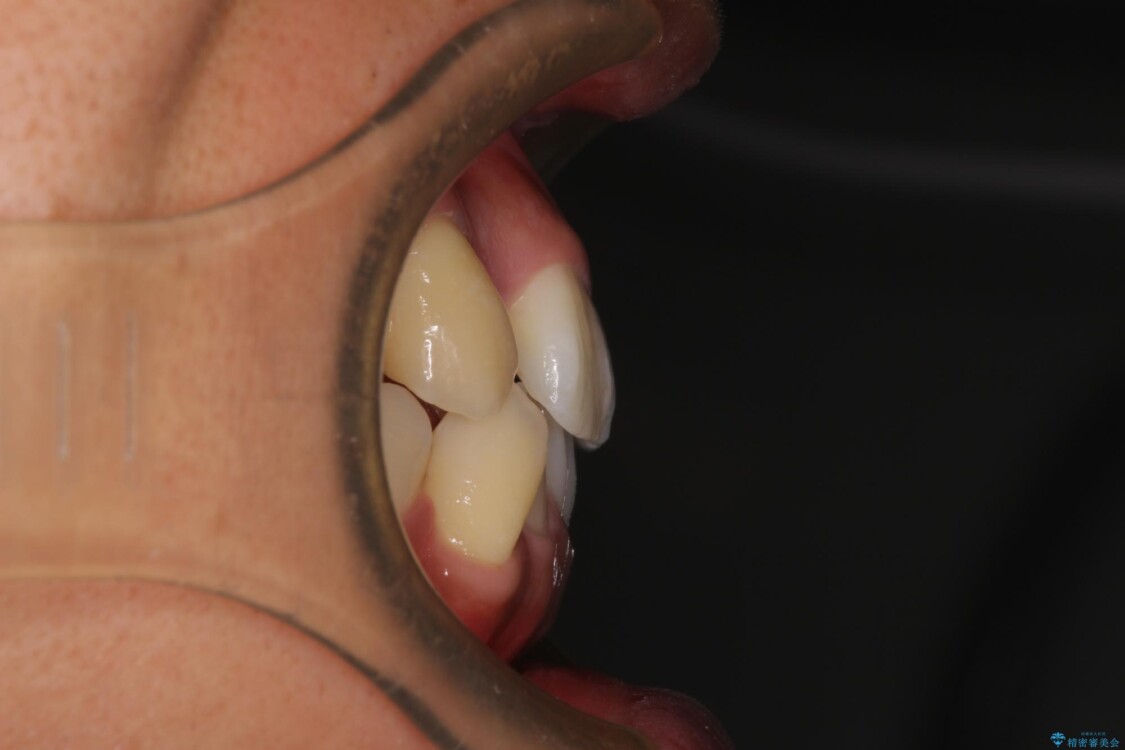

上下の前歯部に強い叢生(ガタガタの歯並び)があり、そのまま歯を並べると出っ歯になってしまう可能性がありました。

そこで、上下左右の第一小臼歯を抜歯し、歯が並ぶためのスペースを確保し叢生を解消する治療計画を立てました。

八重歯はきれいに整い、前歯もバランスよく収まり、横顔のラインも自然に改善されました。

治療前

• 八重歯と前歯のガタガタを抜歯矯正で治療|クリアブラケット使用例 治療前画像